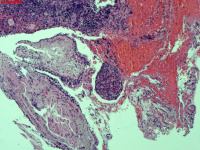

纤支镜咬检

肺TB?Ca?

胸部CT(平扫):考虑双肺感染性病变,结核?支气管炎?请结合临床及其它检查。

标本名称

右肺上叶后段开口咬检组织

大体所见

右肺上叶后段开口处粘膜不规则增生。

肉芽肿性炎的可能性大些!

有坏死,深染变形的细胞需要排一排神经内分泌肿瘤。